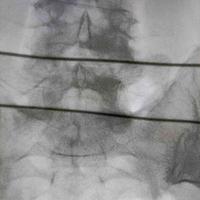

一例腰间盘突出+侧弯

查看图片需登陆

一例腰间盘突出+侧弯...

由 medjpg 发表于 2026-03-24 22:32